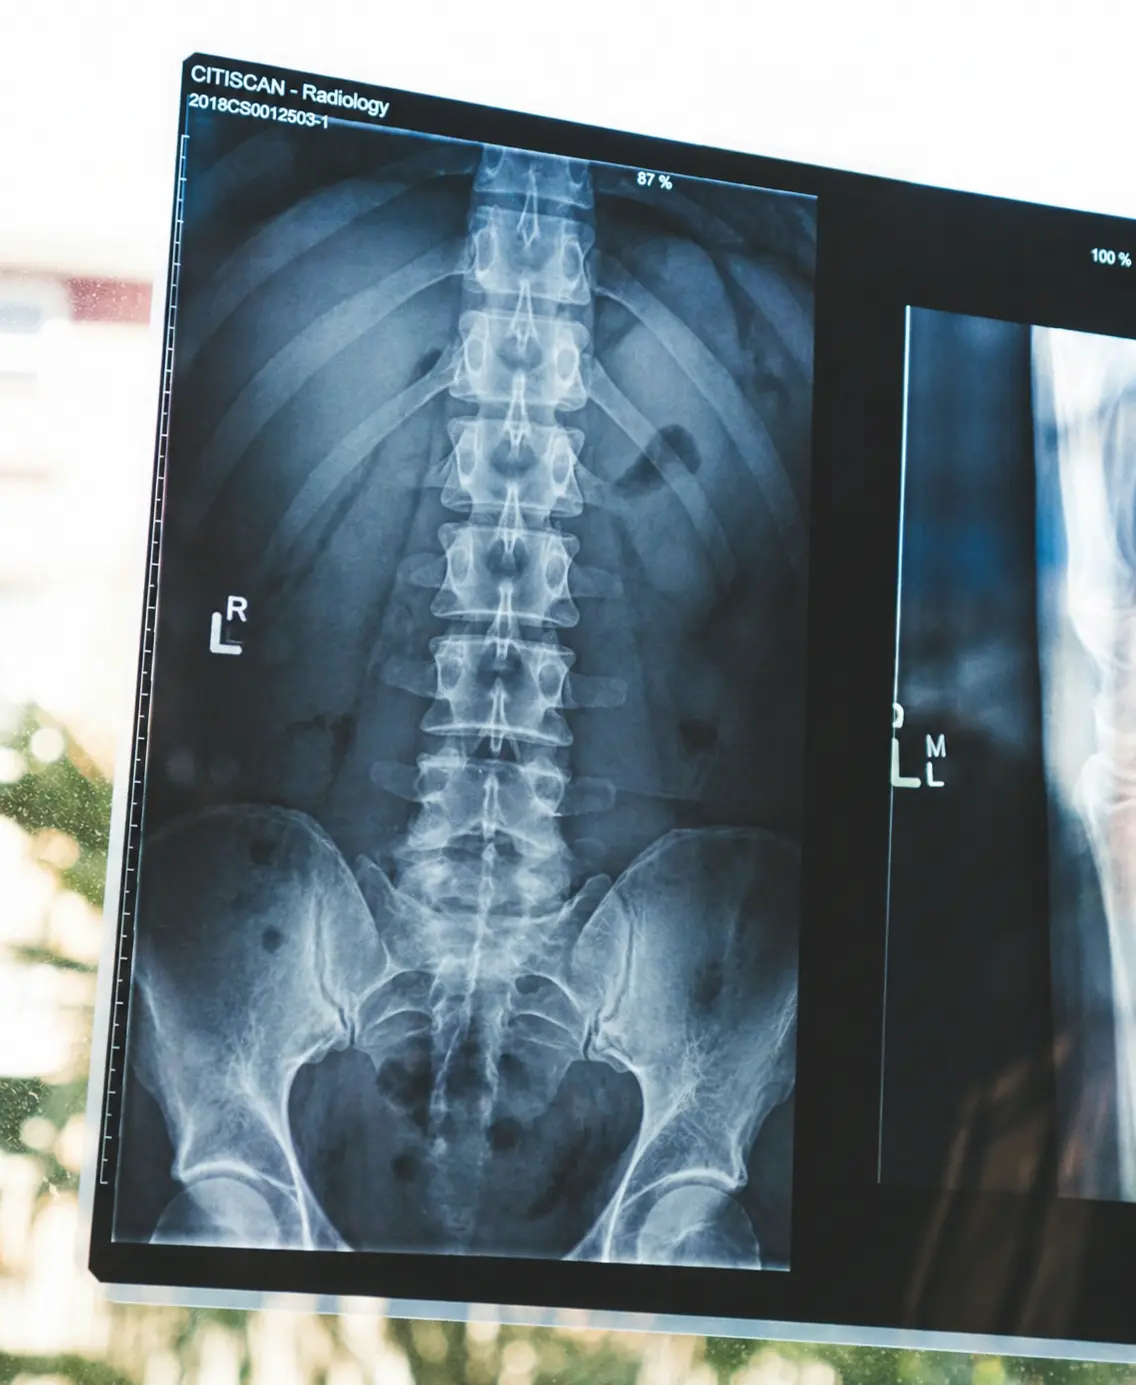

腰痛のうち、画像検査だけでは原因を正確に特定しにくいケースは非常に多く、かつては「85%が原因不明」とも言われていました。現在は診断技術の向上により、丁寧な問診と専門的な評価を組み合わせれば多くのケースで原因部位を特定できるようになっています。それでも慢性腰痛の原因特定は一筋縄ではいかず、「検査で異常なし」と言われながら痛みが続いている方は少なくありません。

検査で異常がないと言われた時、「気のせいなのかもしれない」と思った方もいるかもしれません。しかしそれは気のせいではなく、MRIやレントゲンに映らない部位が痛みの原因になっていることが、慢性腰痛では珍しくないのです。「画像に異常がない=問題がない」ではありません。

画像検査で現在の腰の状態を確認する

X線またはMRI検査で、現在の腰の構造的な状態を客観的に把握します。